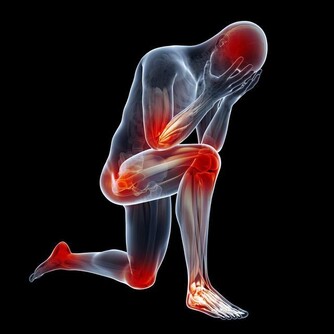

4. 堅持運動,多曬太陽

每天堅持30分鐘以上運動,患癌風險就能有效降低。在適度的太陽光下活動,有利於預防結腸癌和乳腺癌等多種癌症。

記住:最推薦的運動就是走路,最好走路時要做到抬頭挺胸大步走。

還有,多在戶外或者打開窗戶曬太陽。時間一般10~20分鐘即可。